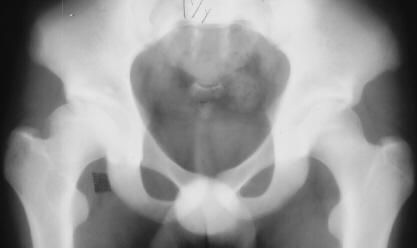

A completely healthy and previously normal boy 10 years and 9 months

old was noted by his parents to limp on the right side after a full day

of activity. He also started to have a occasional hip pain. Since the hip

pain became progressively worse, the family sought medical attention. At

the first examination, abduction was 40 degrees bilaterally but internal

rotation was limited to 0 degree on the right. The leg lengths were equal

and no Trendelenburg sign was observed. X-ray showed the decreased epiphyseal

height and medial joint opening. Snyder sling was started. At 12 years

of age, internal rotation was still limited 20 degrees compared to 35 degrees

on the left side but the left hip pain was asymptomatic. X-rays 1 and 2

were taken at the age of 11 years and 3 months and xray 3 was taken at

12 years of age. At 16 years of age, 10 degrees limitation of internal

rotation as compared to the opposite side was still observed but the patient

was asymptomatic. X-ray 4 was taken at 17 years of age.